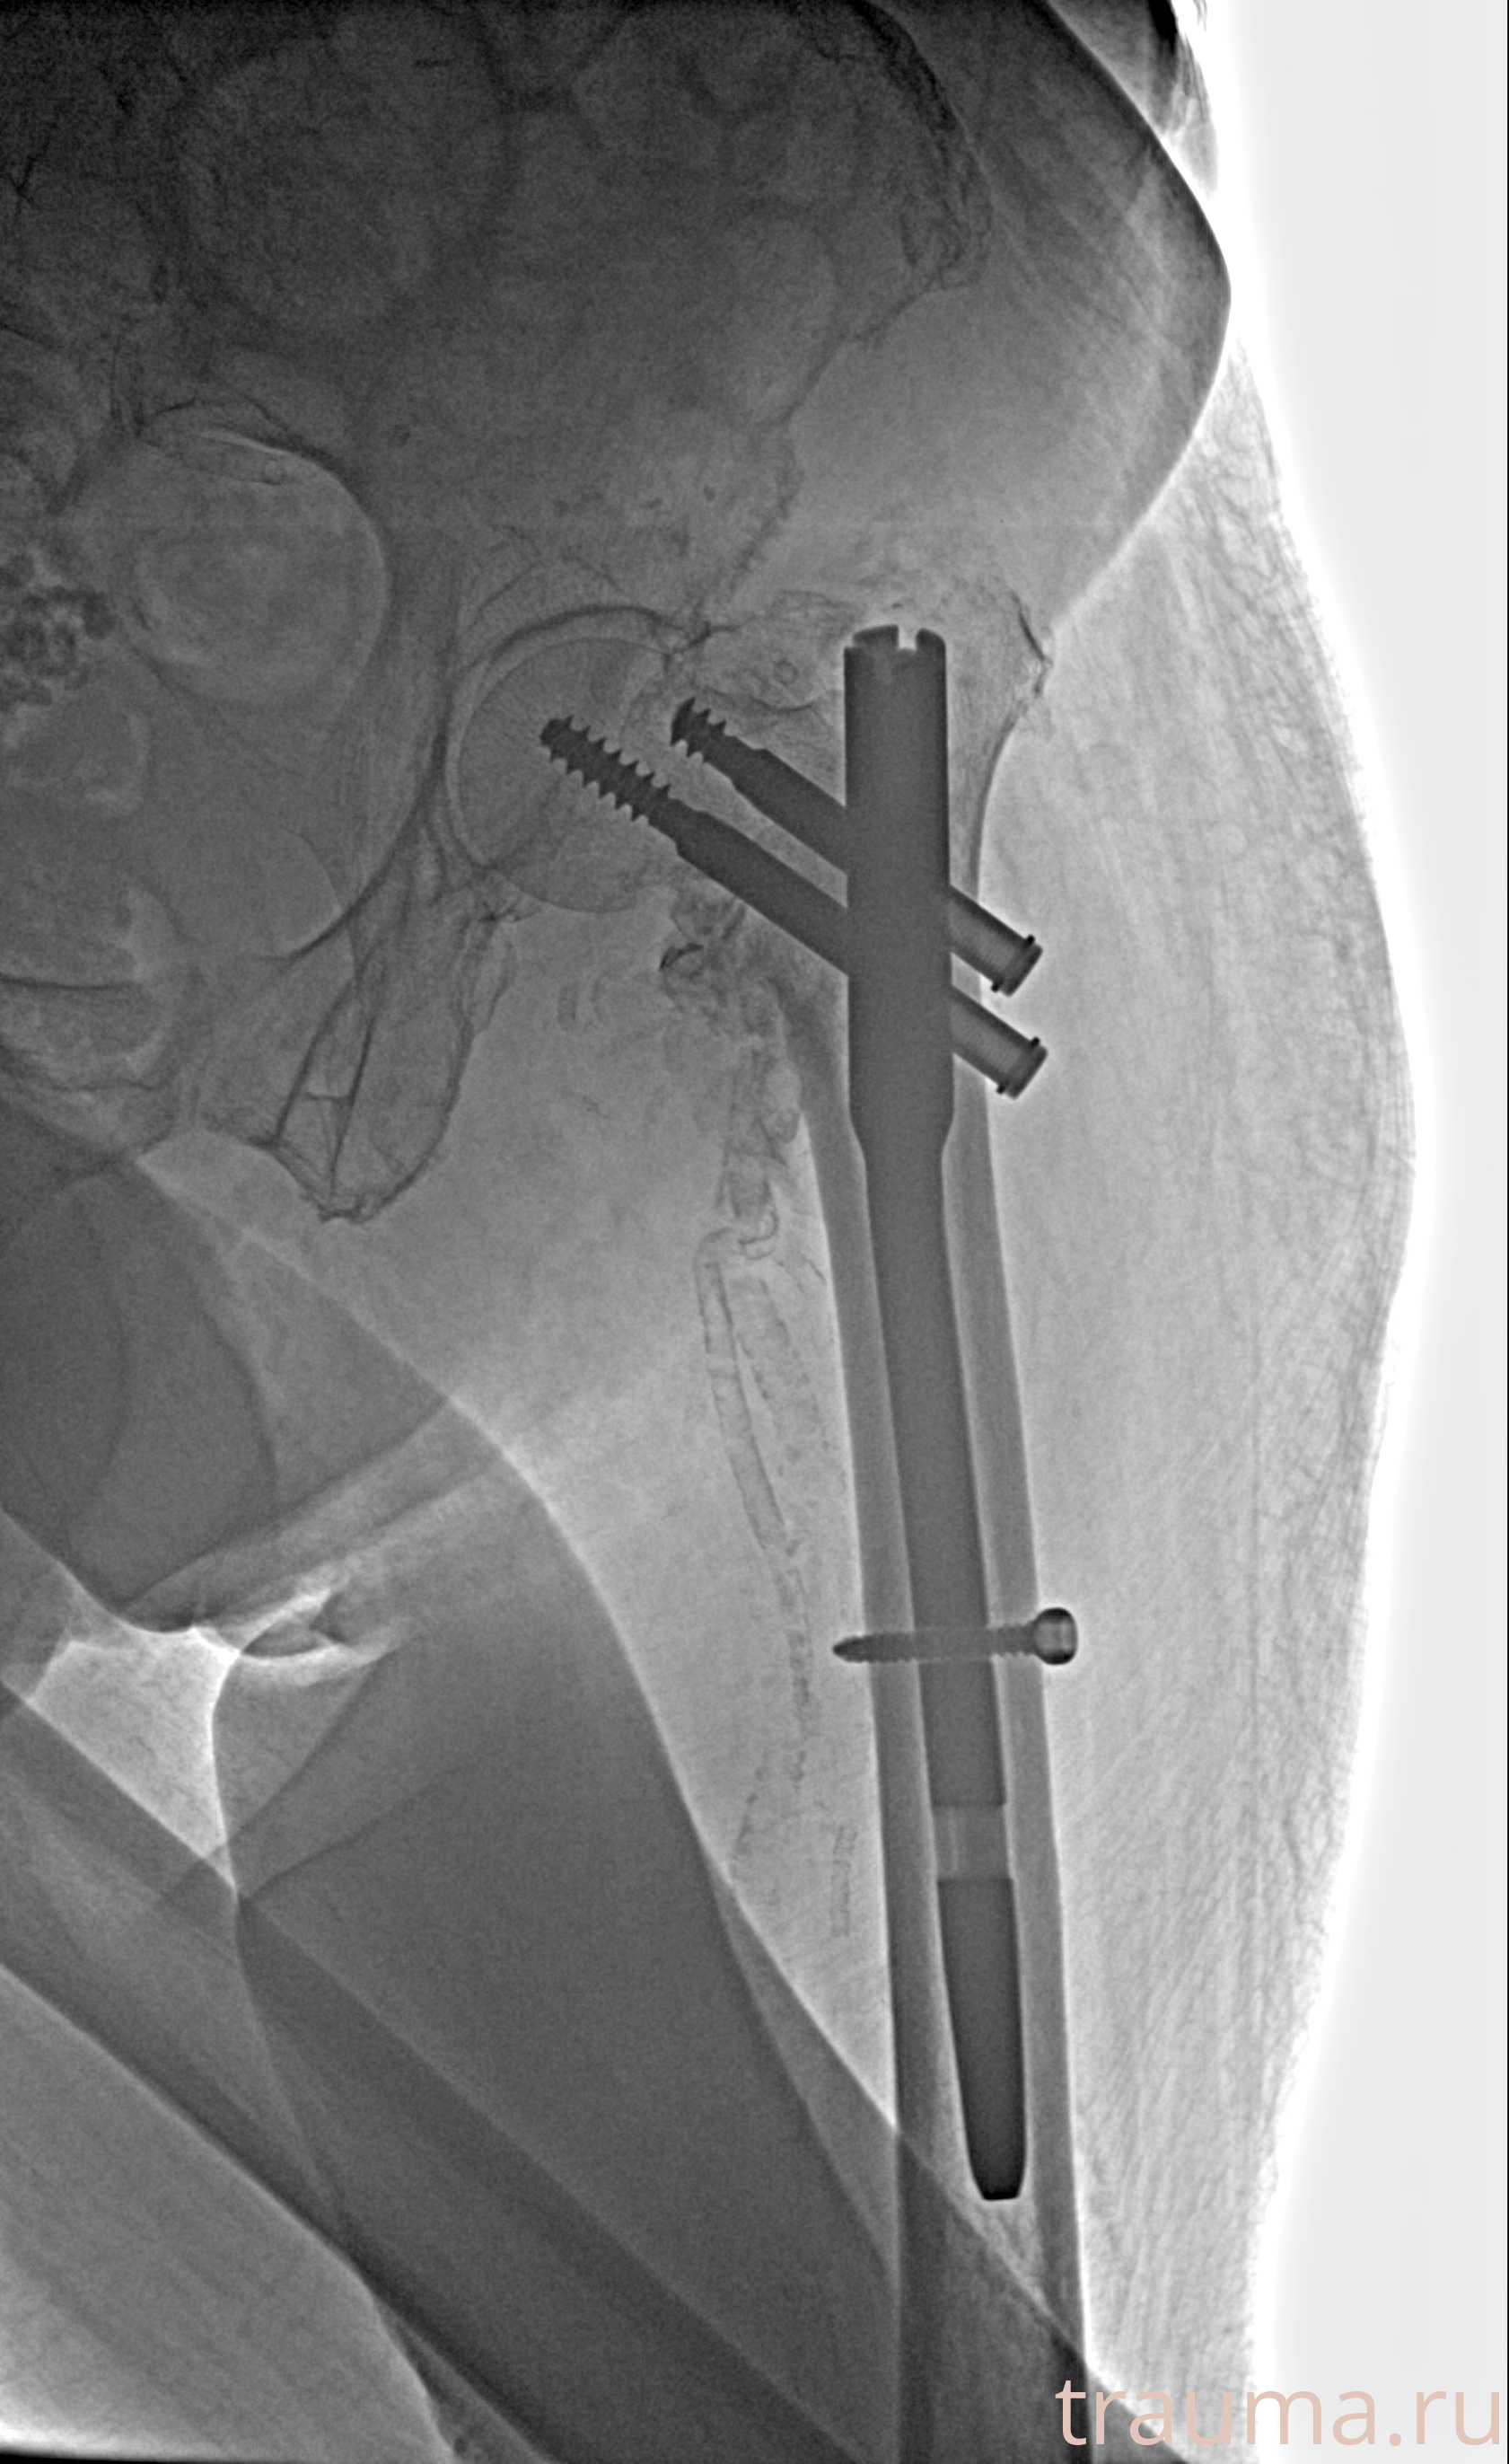

Рентгенограммы

Рентген на дому: по вашему адресу приезжает врач-рентгенолог, травматолог-ортопед с мобильным рентгеновским аппаратом, проводит диагностику травмы или заболевания, делает необходимые рентгенограммы, дает рекомендации по дальнейшему лечению. Получить качественные снимки в домашних условиях возможно благодаря уникальной методике, разработанной МосРентген Центром для института  Склифосовского